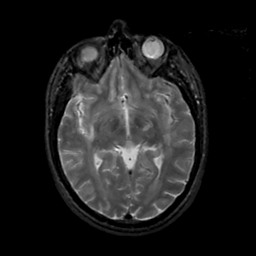

MR Study #12, May 12, 1991 -- Slice #23